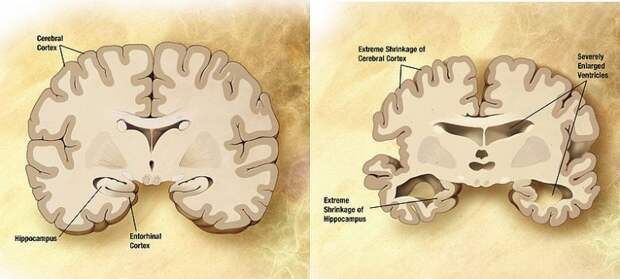

«Это имеет смысл, ведь известно, что обонятельная луковица, связанная с чувством обоняния и энторинальной корой, запоминает и определяет запахи, она входит в число первых структур головного мозга, которые прежде всего и затрагивает болезнь».